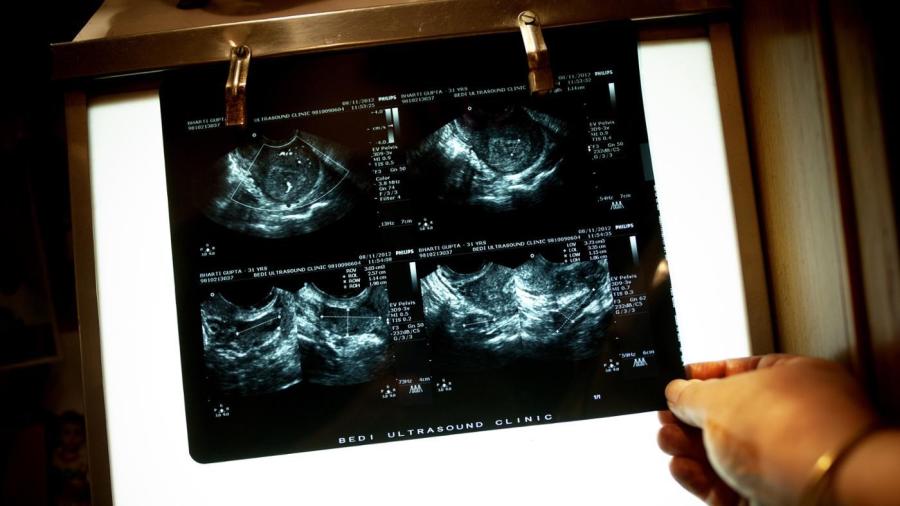

Ultrasound scanning is a safe way to view images of a developing baby inside a pregnant mother’s uterus, Dr. France explains. This method is called “pre-natal scanning” or “fetal imaging,” and it helps to confirm the health of a baby. Ultrasound scanning works by directing ultrasound at the body, allowing the surfaces of various tissues inside the body to reflect the ultrasound. Depending on the depth of the tissue surfaces, a detector receives ultrasound echoes at varying times and sends electrical signals to a computer. An image is then produced and displayed on a screen.